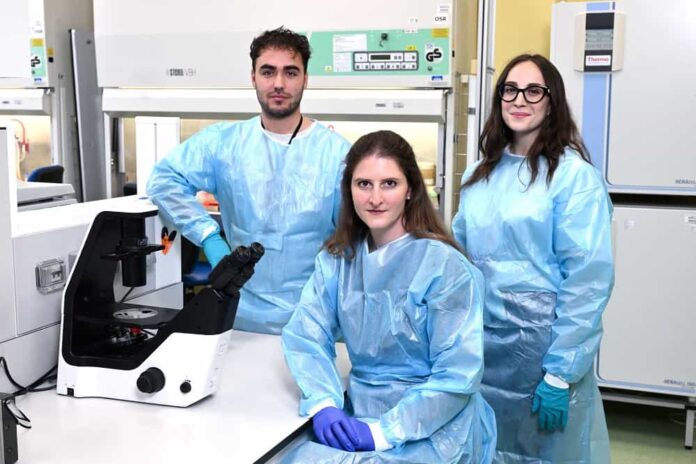

“Immunotherapy has transformed the treatment of advanced solid tumors, but its effectiveness is still limited to a minority of patients,”

explains Dr. Chiara Maria Cattaneo, lead researcher.

“With Chewbacca, we aim to overcome current limitations by offering a tailored therapeutic response based on each patient’s unique immune profile”.

“Developing immunotherapies that activate the immune system against each individual tumor is one of the most promising frontiers in oncology. We’re proud to pursue this challenge with a young researcher and the support of Fondazione Veronesi”.